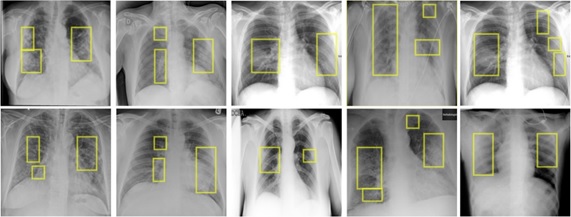

An Automated Framework for Corona Virus Severity Detection using Combination of AlexNet and Faster RCNN

Muhammad Haris Munir Haris, Rabbia Mahum, Muhammad Nafees, Muhammad Aitaza, Aun Irtaza

197-209

Report Generation of Lungs Diseases From Chest X-ray using NLP

Shagufta Iftikhar, Iqra Naz, Anmol Zahra, Syeda zainab Yousuf Zaidi

223-233